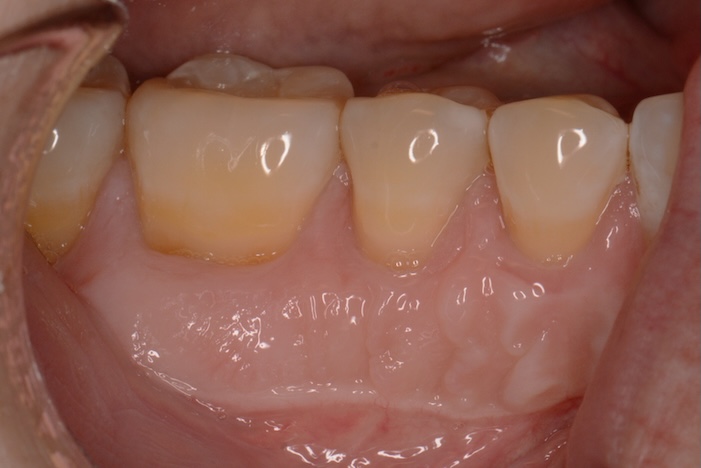

Kim was afraid to have her receding gum line fixed. Dr. Martin used a minimally-invasive gum grafting technique to renew her smile.

A big concern for your oral health, functionality, and appearance, is receding gums. To restore your smile, we use gum grafts. This process works by using graft tissue to cover the exposed roots, protecting your smile.

Gum grafts can be a cosmetic solution but are also a common treatment after periodontal disease. They take the longest to heal from but are one of the more versatile treatments after suffering from gum loss.